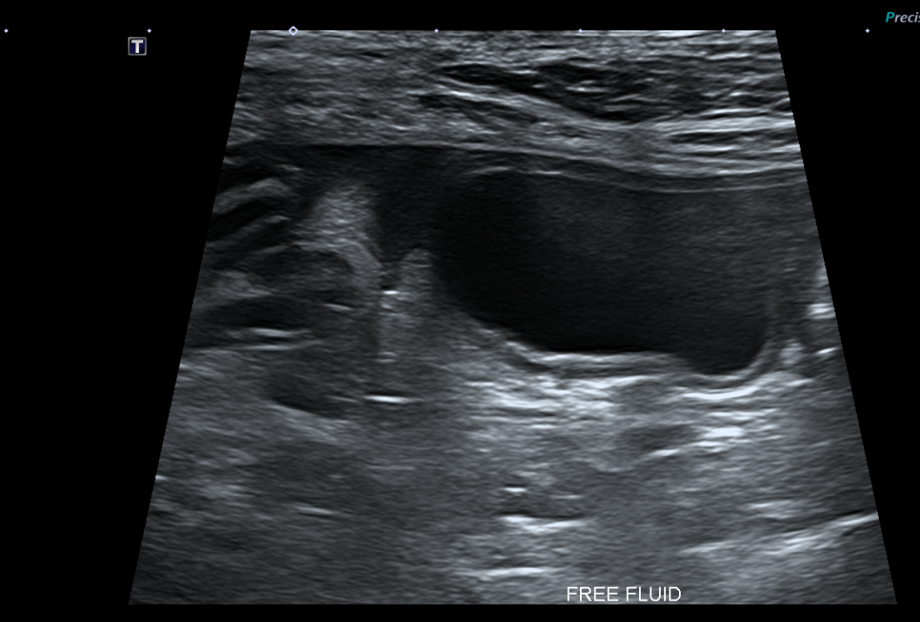

복부초음파

또한 복부 초음파상에서 뚜렷한 췌장 비후, 저에코성 음영, 주변 복막의 고에코성 소견 -> 확인되어 췌장염이 강력 의심되는 상황이었습니다.

Figure 2. 췌장 비후와 주변 복수 확인됨.

환자의 경우 뚜렷한 소화기 증상, 뚜렷한 염증 소견과 QPL 수치 상승, 복부초음파상 췌장염 비후, 복수 소견 확인되어 췌장염으로 진단되었습니다.

- 췌장 주변 Fluid 축적

하지만 복부 초음파를 통해 췌장 주변의 국소적인 합병증 (예: Extrahepatic Bile Duct Obstruction, EHBO)을 평가하는 데 매우 유용합니다.